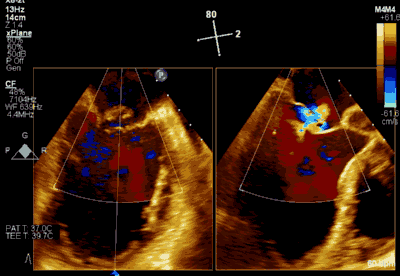

▲ 术后超声检查显示轻度二尖瓣反流